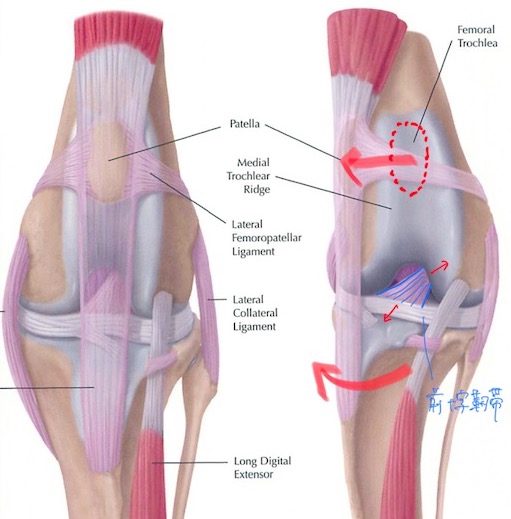

また、膝蓋骨の脱臼が慢性的に起こっている膝関節では関節が内側に引っ張られる力がかかっているため、膝の中の靭帯(前十字靭帯)に負荷がかかっており、年齢を重ねるにつれてダメージが蓄積し、将来的に靭帯の断裂を招いてしまうリスクも考えなければいけません。(赤矢印)

X線を見ると、膝蓋骨が本来あるべき位置(赤点線)から内側に脱臼してしまっていることが分かります。(黄色)